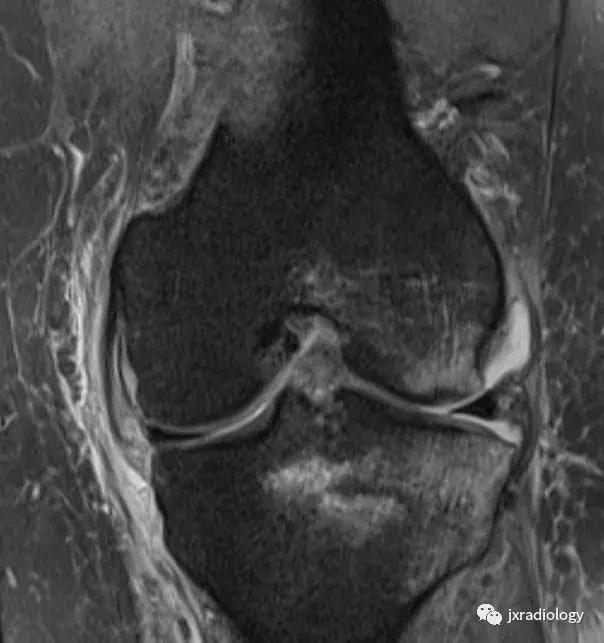

图27:废用性骨质疏松症(DO):在骨骺上的所有序列中显示的融合和斑片状中-高信号影是典型的长期固定后的短暂性骨质疏松症。恢复活动在废用骨中产生比在正常骨中更大的应力,因为必须支撑负载的骨小梁更小更弱,因此出现骨髓水肿(应力反应也在内侧髁上看到并用* 标识)。一个愈合的外侧胫骨平台骨折(箭头)。 (a-e:PD-FS-WI; f:T1-WI)。值得注意的是,复杂性局部疼痛综合征(CRPS,包括包括反射*交性**感神经营养不良,痛觉神经营养不良和Sudeck骨萎缩)具有与DO相同的MRI骨水肿模式,但其病理生理学与废用脱钙无关,并且总是伴有疼痛(DO是无症状患者的偶然发现,在有外固定的患者中)。